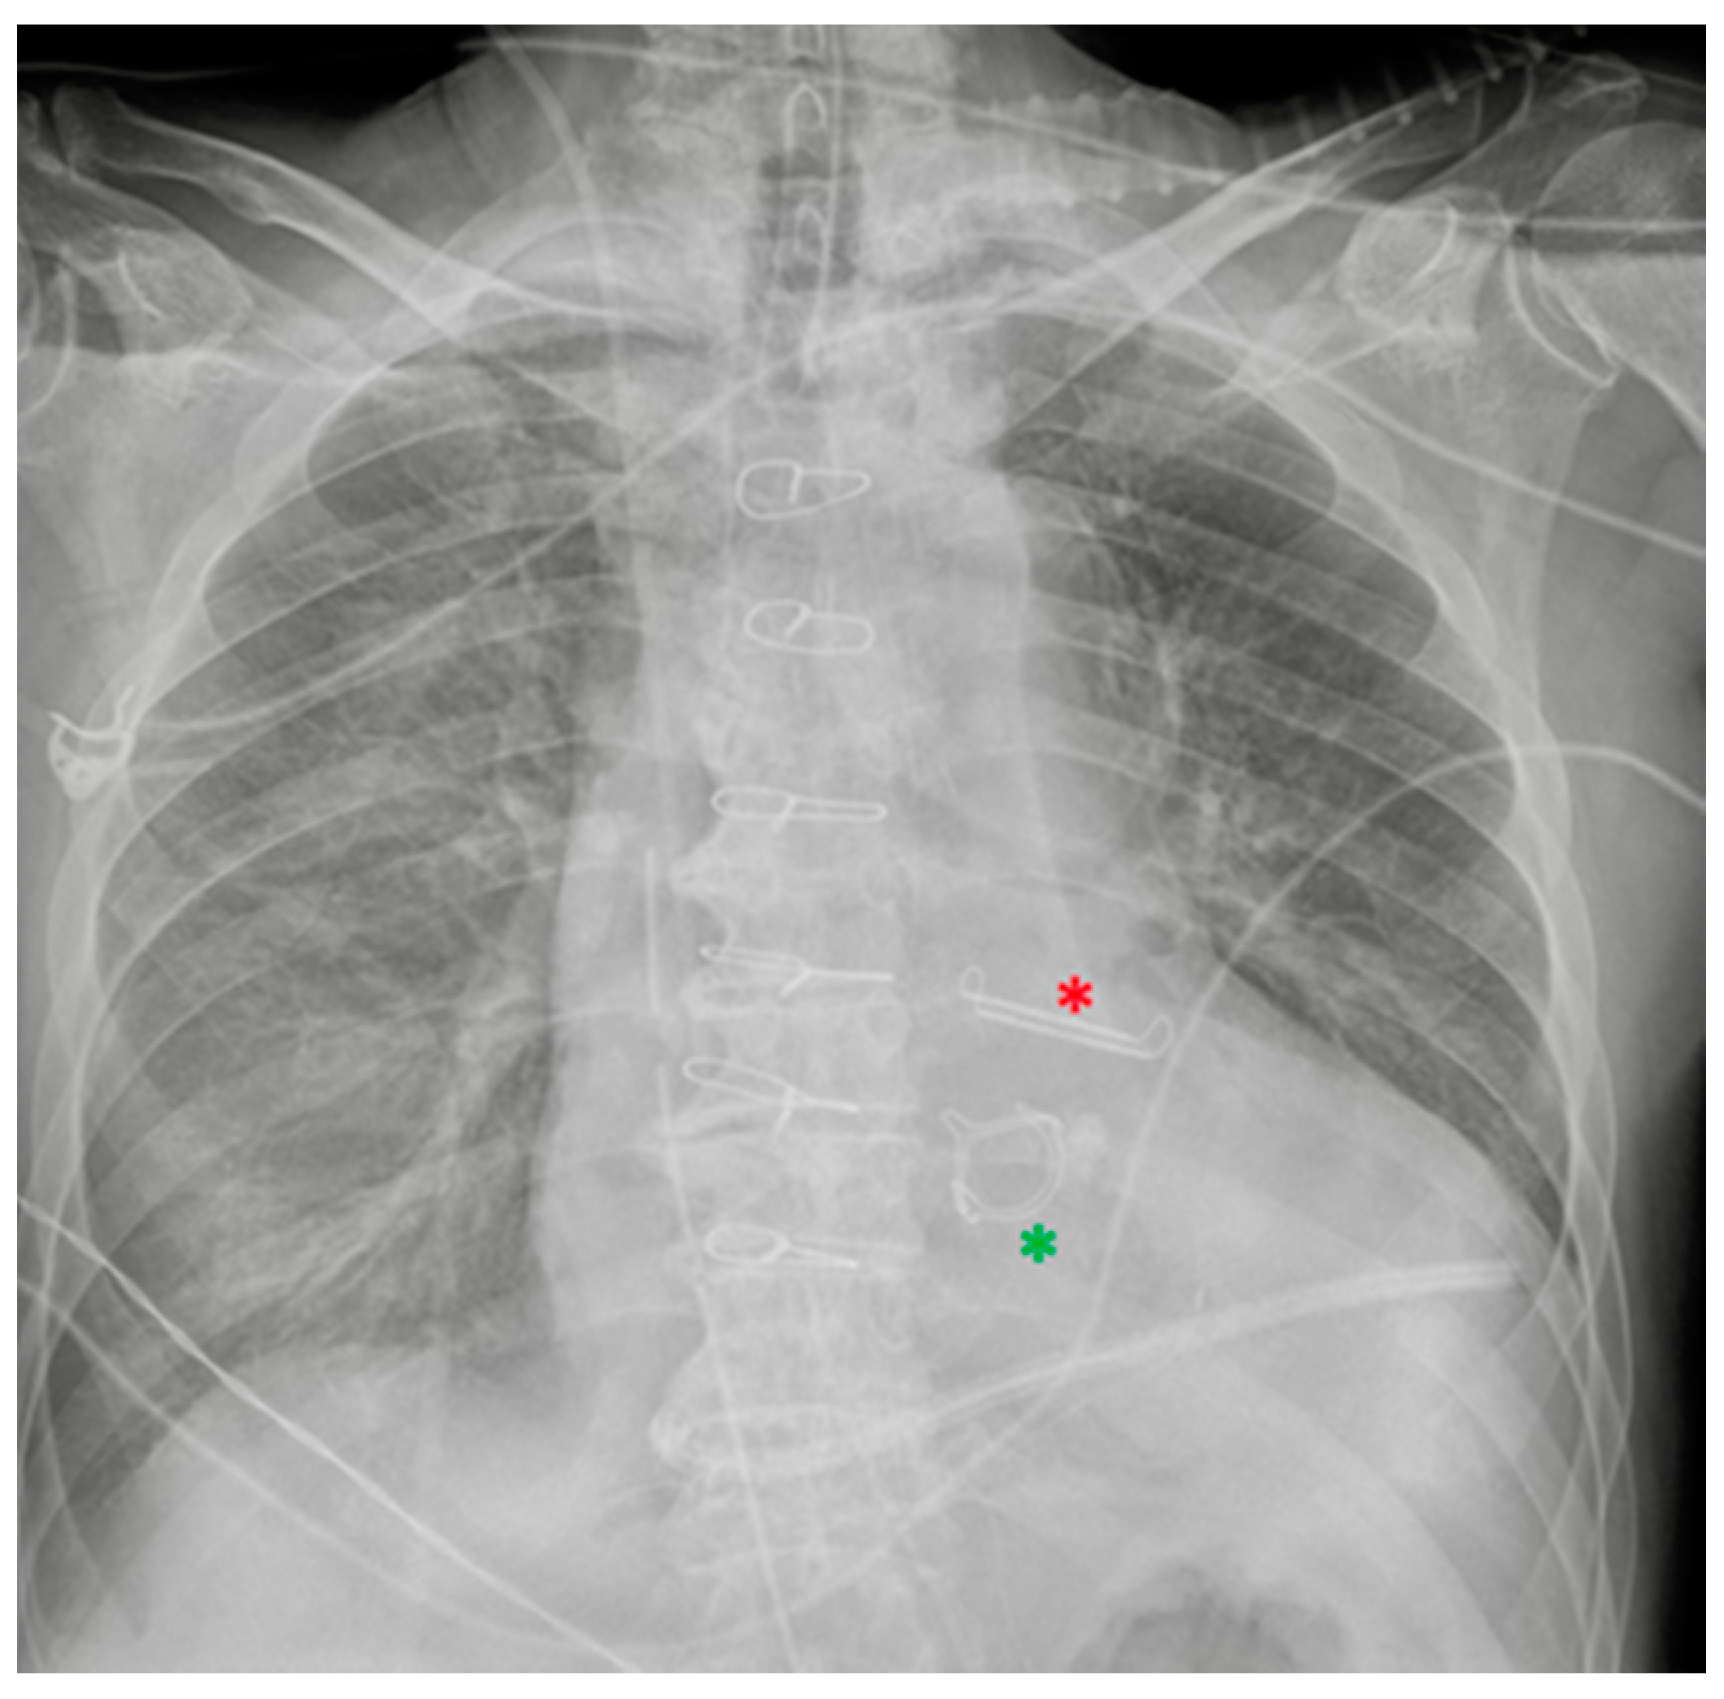

Left atrial appendage closure device (red asterisk). Prosthetic biological mitral valve (green asterisk). the image also shows right jugular CVC, ETT, NG-tube, chest tubes and sternal wires.